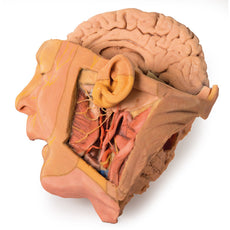

In contrast to the HW 44 specimen, this model has a more expansive superficial

dissection inferior to the external ear and across the posterior scalp and occipital region. This allows for an

expanded appreciation of the neurovascular distribution of the supraorbital and supratrochlear nerves and arties

with the superficial temporal artery. Inferior to the ear, the retromandibular vein has been exposed with the

ascending fibres of the great auricular nerve on its superficial surface (and further branches of this nerve on the

surface of the sternocleidomastoid muscle). At the posterior border of the sternocleidomastoid muscle the lesser

occipital nerve is just preserved, near the exiting and ascension of the occipital artery and vein near the

trapezius muscle towards the posterior scalp. Surrounding the external ear are fibres of the auricularis superior

and posterior muscles. Near the margin of the dissection window posteriorly the deep fibres of the occiptalis muscle

can be seen integrated into the epicranius (occipitofrontalis) muscle.